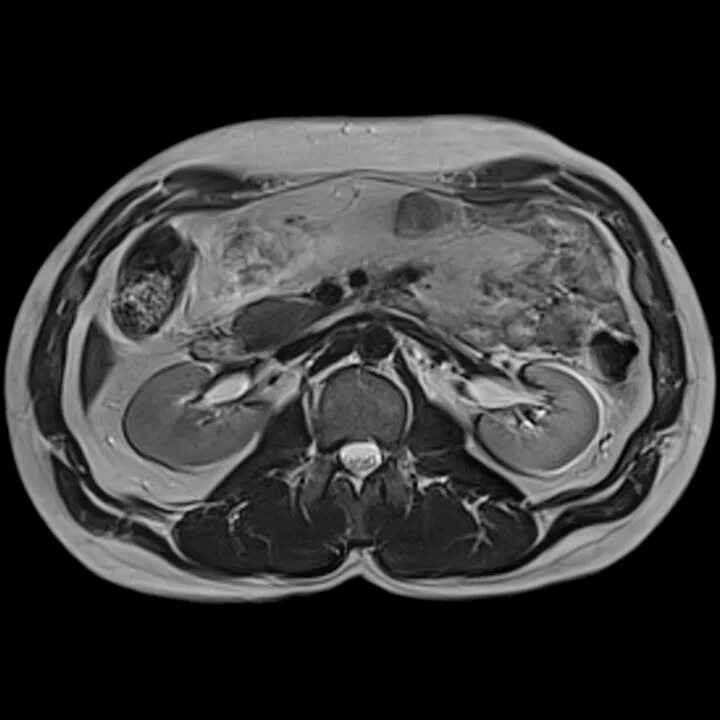

Мрт обп с контрастированием